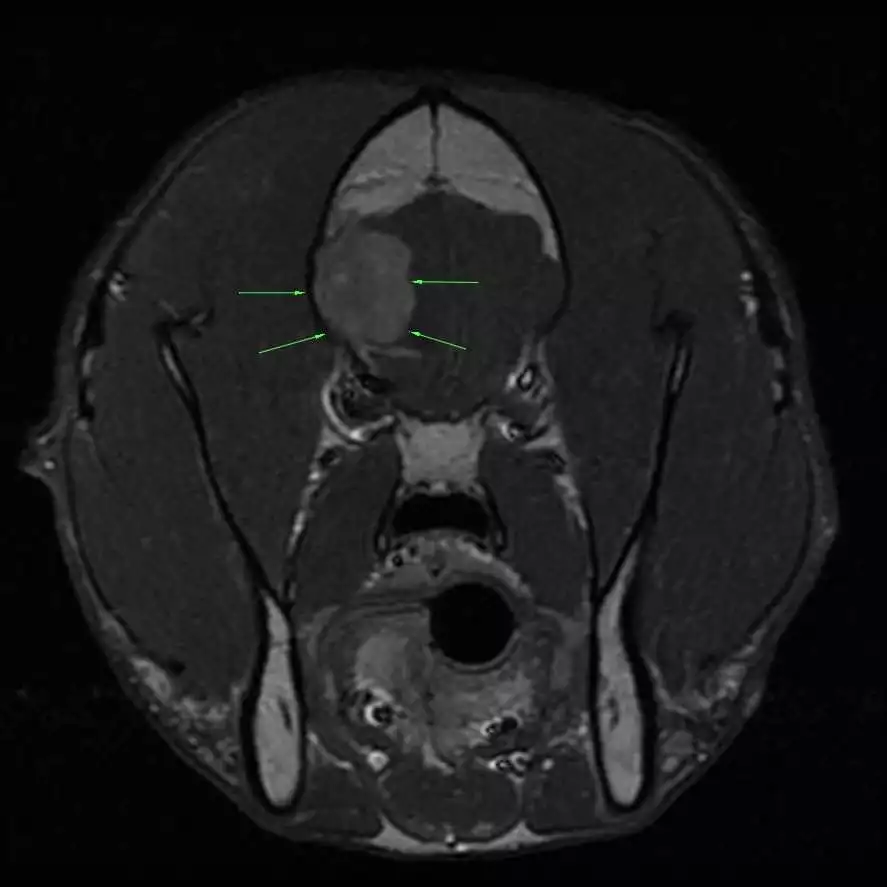

Pre-Operative MRI In Dog With Brain Tumor

The most common type of brain tumor in dogs and cats is called a meningioma. Meningiomas tend to be benign, located on the surface of the brain, and removable with surgery. This surgery can be curative for cats, while dogs can live for several years.

We will only recommend surgery if we feel that the potential for a good outcome outweighs the risks. After performing an MRI, your veterinary neurologist will let you know whether brain surgery is a good option for your pet.